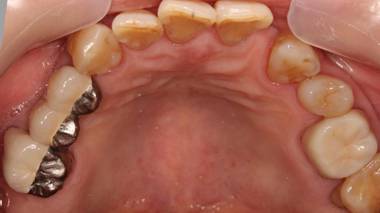

術後。上部構造はハイブリッドレジンです。しっかり嚙めるようになり喜んでいただきました。

上顎

上部構造装着後6年。ハイブリッドレジンを使用したため、少し艶がなくなってきました。上部構造の材料には金属、ハイブリッドレジン、セラミックなどがあります。セラミックはきれいですが欠けやすいため、最近はフルジルコニアを使っています。

上顎 少しすり減ってきました。